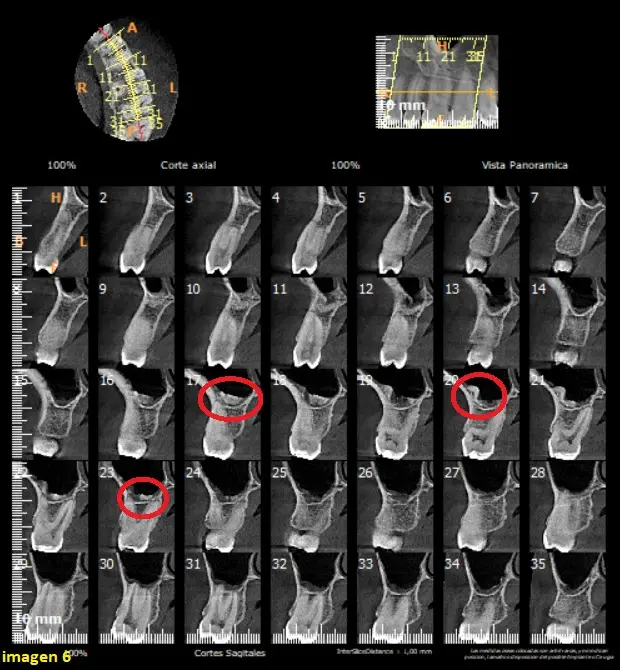

Luego de obtener las imágenes, podemos observar en zona de piso de seno maxilar izquierdo, una imagen hipersensa, que se confunde con la cortical, parece estar fusionadas a la pared lateral mismo. (ver imagen 2)

En el corte coronal, podemos observar imágenes de densidad cálcica a nivel del piso del seno maxilar (flechas rojas) con densidad semejante al hueso y que parecen estar fusionadas con el piso del seno maxilar. (ver Imagen 3)

En el corte tangencial del seno maxilar izquierdo, hacia nivel vestibular, podemos observar la calcificacion sobre la raiz de la pieza dentaria 26 (circulo) y un leve engrosamiento de la membrana sinusal del seno (flecha blanca) (ver imagen 4)

En el corte axial del seno maxilar izquierdo, a nivel inferior, podemos observar la fusion de la calcificacion, en la pared lateral del seno maxilar izquierdo, rodeada de un halo hipodenso vinculante a mucosa sinusal. (ver imagen 5)

Signos tomograficos compatibles con ANTROLITOS.